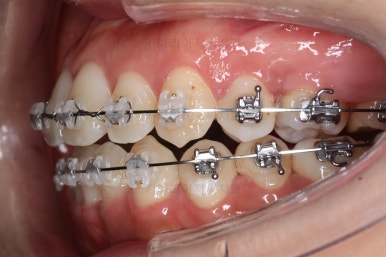

교합과 중앙선 및 디테일을 맞춰 나갑니다.

중앙선, 교합, 앞니 맞물림 등 모든 것이 좋아졌네요.

교합, 정중선 모두 좋아졌고요.